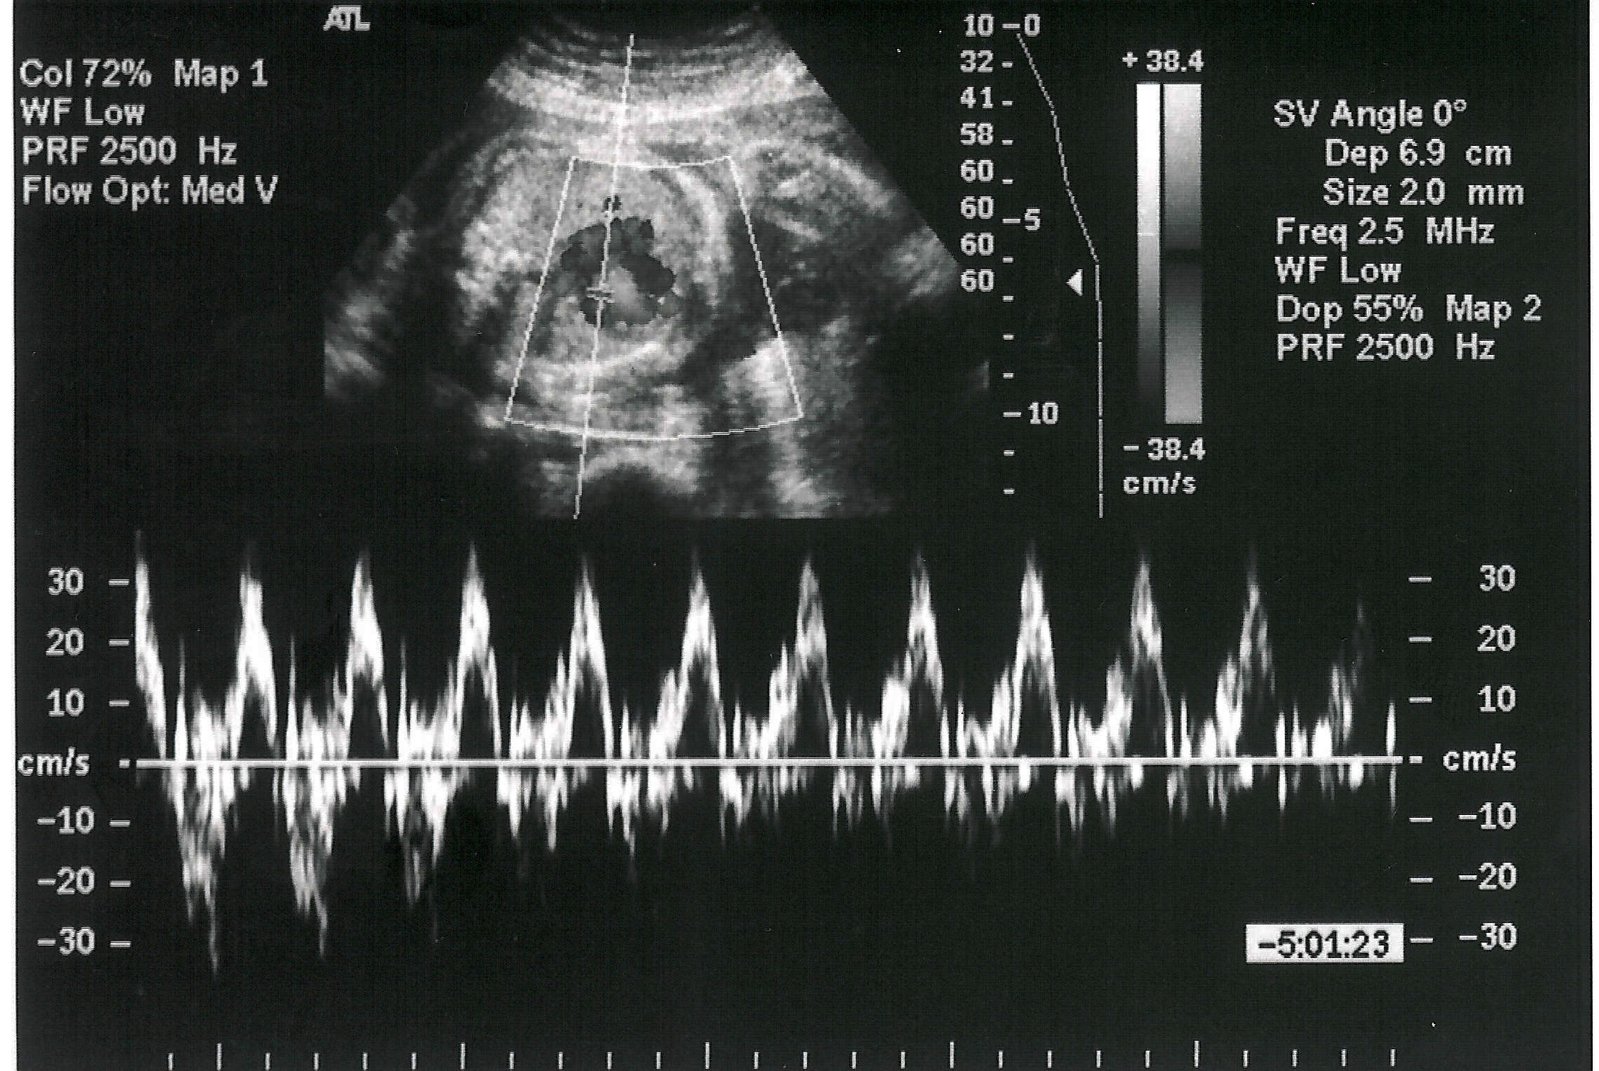

Zanimljivo je da su normalni otkucaji srca kod beba u trbuhu čak dvostruko brži od otkucaja kod odraslih osoba. Koliko je normalan puls srca kod odraslih osoba. Puls od 60 90 otkucaja u minuti se za žene smatra normalnim. Otkucaji srca bebe u trudnoći se također razlikuju od odraslih ali i od novorođenčadi.

Kod žena u trudnoći normalan je i blago povišen rad srca kao i tijekom umjerene fizičke aktivnosti kada broj otkucaja srca u zdravih odraslih osoba iznosi između 120 i 130 otkucaja u minuti. Sa druge strane kod odraslih osoba povećan broj otkucaja srca u stanju mirovanja ukazuje na prisustvo određenih zdravstvenih problema i predstavlja apel da se što pre obratite lekaru. Puls koji je van ovih. Tokom trudnoće srce pumpa između 30 i 50 procenata više krvi u odnosu na negravidno stanje.